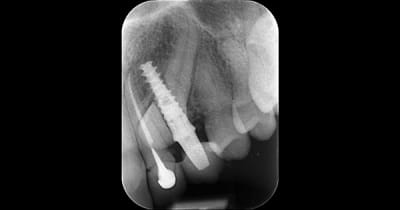

@ Hokusai

Là aussi on est très proche. Trop d'ailleurs.

Ca s'est mal terminé.

Je me souviens d'une conf à l'ADF d'un praticien qui affirmait avec beaucoup d'aplomb qu'il n'y avait aucun problème à transfixer des racines. Depuis j'ai vu ce cas, et j'ai un peu plus de doutes.

Xjl7j1xqmc1kk7je5jdwm8lmi36c - Eugenol

1cehfyo452d8vb4e4rhx349l17tv - Eugenol